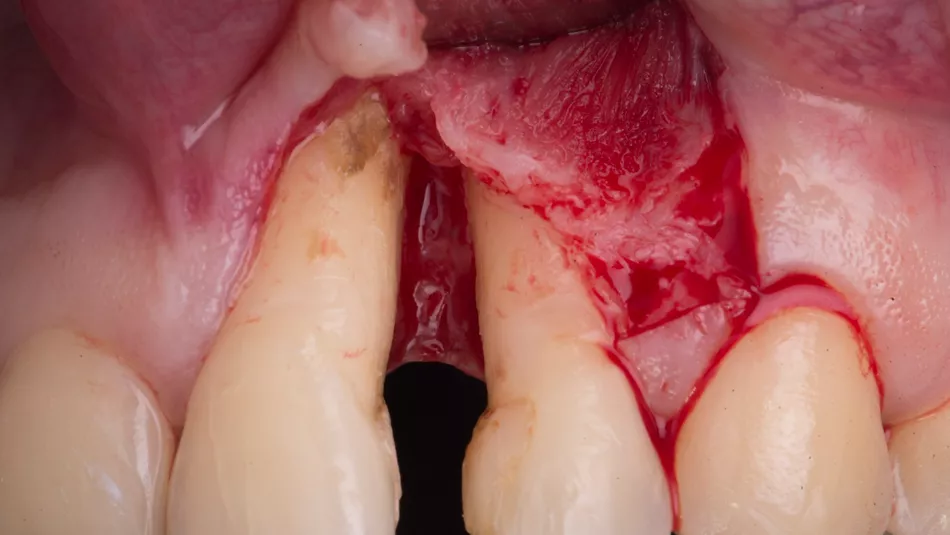

A CTG wall technique was conducted with a release incision at the distal aspect of the lateral incisor (Fig. 3).

Fig. 3